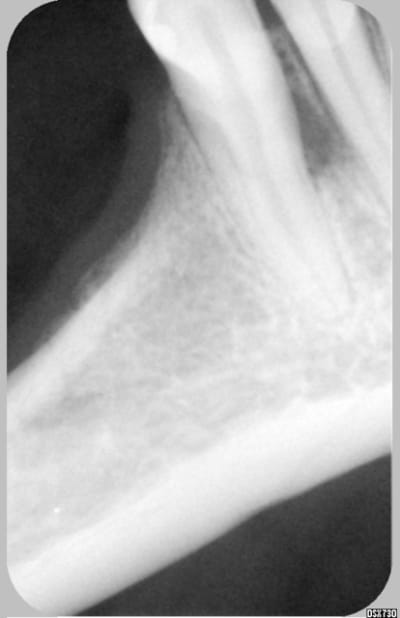

Patiente la cinquantaine, venue avec abcès en vestibulaire entre 33 et 32.

Stellite de 37 à 34 et de 47 à 45.

Lors du 2° rdv, plus de douleur, test au froid positif sur 33, 32, 31. Pas de réaction exploitable au chaud. Percution à peine plus sensible sur 32. Sondage normal autour des dents.

L'image montre une raréfaction osseuse entre 33 et 32.

t'as pas une radio plus precise de l'espace interdentaire ,une photo de bouche? les sepas des autres dents me paraissent un peu douteux tout de même .

Ton stellite il passe comment en lingual ? n'y a t il pas un rapport ?

C'est vrai qu'il y a atteinte du parodonte c'est evident mais ici il semble qu'il n'y ait pas de poches ( c'est ce que dit le roi de la gutta donc cela n'est pas comme ton cas. quelle est la cause? Le stellite comme je le pensais ?

Je maintiens, poche serpengineuse à point de départ lingual, d'autant plus que la connection métallique passe en face et appuye sur la gencive oedématiée à cet endroit avec effet de pompe pendant les fonctions,...

Mais cher amibien s'il s'agit d'une poche, même à départ lingual, il devrait y avoir un sondage positif au moins en un point, non ?